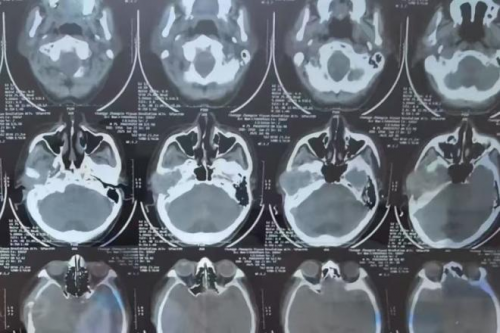

接诊张大爷的是郑州民生耳鼻喉医院特聘专家娄卫华教授,这是一位国内知名耳鼻喉科专家。根据患者的病史描述和一系列影像学检查结果,包括CT影像和耳内窥镜分析,娄教授最终发现张大爷右侧颞骨处存在明显肿物。结合症状表现,判断为“右侧颞骨肿瘤”。为了进一步确认肿物性质并制定针对性的治疗方案,手术切除成为必要步骤。

颞骨区域结构复杂,与多条重要神经和血管紧密相连,增加了手术实施的难度。若操作稍有不慎,可能会引发面瘫或听力丧失等严重后果。因此,为确保手术安全,娄卫华教授组织医疗团队进行了详细的术前讨论,结合患者年龄、身体状态以及病情特点,制定了精准且微创的手术方案,既能完整切除肿物,又尽量保护周围正常组织。